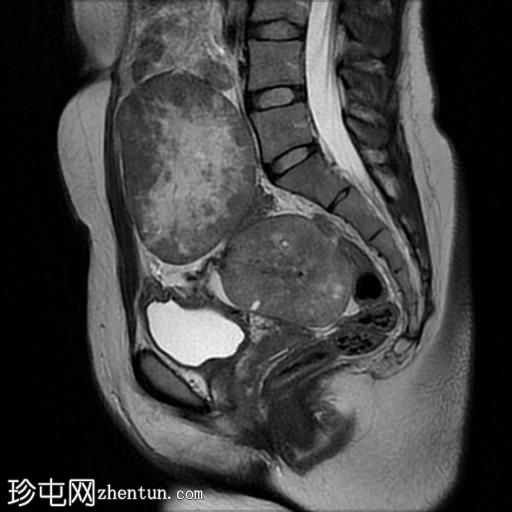

矢状位

T2加权像

盆腔内可见多个边界清晰的肿块:

其中一个位于子宫上方,T2加权像呈中等信号,中心区域呈高信号,增强T1脂肪抑制像未见强化。右侧卵巢增大,增厚的血管蒂扭曲,未见强化,轴位和矢状位T2加权像均显示清晰。

另一个位于子宫后窝,T2加权像呈中等信号,增强扫描显示明显强化。

轻度腹腔积液